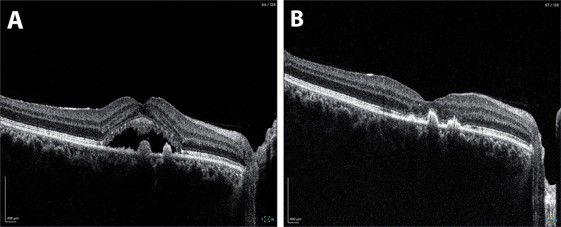

Fig 2. A. At baseline, OCT through the right fovea demonstrates subretinal fluid with small hyper-reflective pigment epithelial detachments. B. Following laser, there has been complete resolution of subretinal fluid at the fovea.

The results were notable from an anatomical standpoint. At two-month follow-up, OCT demonstrated complete resolution of subretinal fluid, while autofluorescence imaging confirmed preservation of RPE integrity at the fovea with no treatment-related damage.